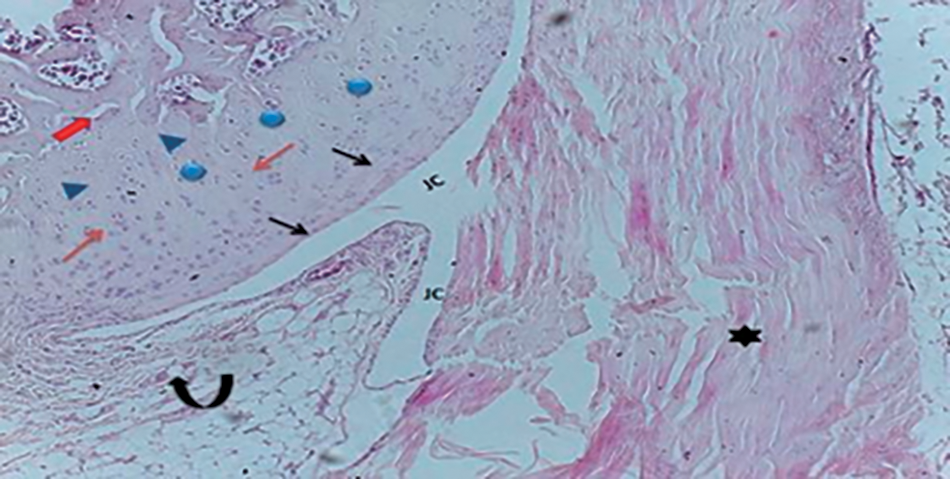

Sections from the control knee joint revealed that synovial cavity lined with thin membrane known synovium it was connective tissue lined the inner surface of synovial joint capsule and, with direct contact with fibrous membrane formed many folds extend into the joint cavity from the connective tissue of the capsule, the joint cavity itself appeared highly vascularized with specialized cells (synoviocytes) observed, one type attached the tissue surface are large, rounded, macrophage like synoviocytes (type A) showed as cells formed layer like the epithelial layer at the cartilage surface, while the other type known fibroblast like synoviocytes (type B), epiphysis growth plate from control rat showed the growth plate structure composed of resting cells, proliferation chondrocytes, ossification zone with thin bone spicules separated by marrow cavities (Figs. 8–10).

Fig. 8. Photomicrograph of normal articular cartilage showing the variable zone of cartilage, superficial (), middle (), deep (), and calcified zone (), the chondrocytes showed heterogeneity in size and some with lacuna (), fibrous capsule () and normal synovium () extend as fold to the joint cavity (JC) (H & E) stain.